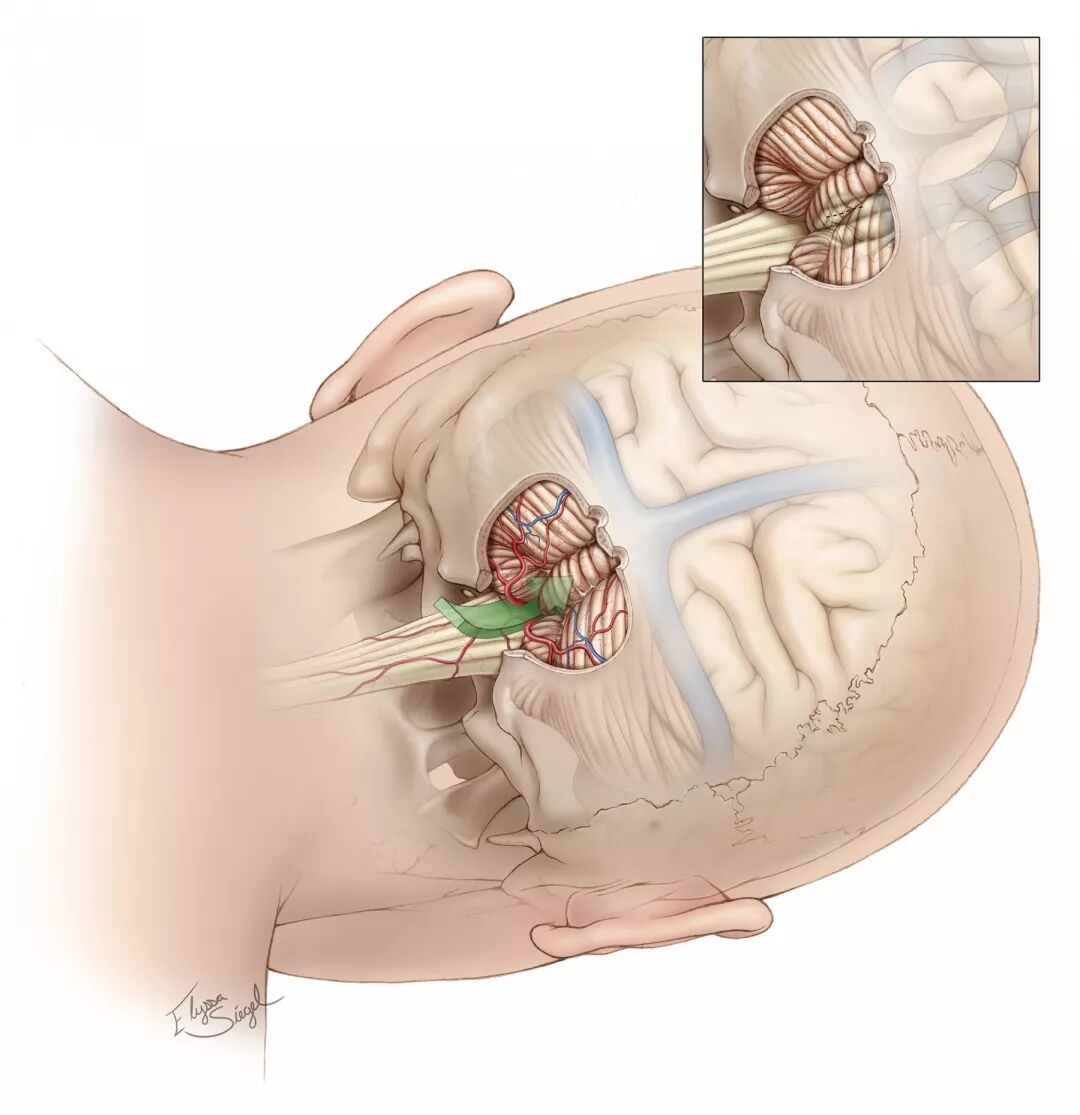

图8:图示膜髓帆入路的手术分离通路。注意枕骨大孔已打开,小脑扁桃体、小脑蚓部与小脑半球内侧面已显露。内嵌图显示第四脑室结构与其表面小脑的关系。

图9:若CM在脑干表面明显可见,就能开始切除病灶。但若CM在表面不明显,需描记面丘来避免损伤。应避开舌下神经与迷走神经三角,除非病灶有外生部分,并已使这些结构移位。

图10:双极电凝镊的动态移动能避免手术残腔在分块切除CM时塌陷。需轻柔地固定牵拉小脑扁桃体,从而能在脑干内双手分离。